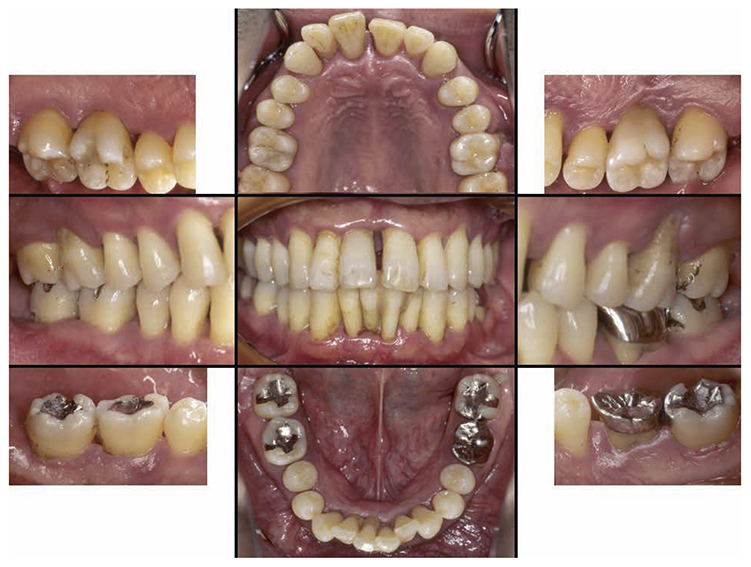

No obvious redness and swelling were present in the marginal gingiva across the full jaw; some blood congestion was however observed. The gingival shape of the anterior teeth in the mandible and maxilla was that of a thick shelf. Significant gingival recession was observed on the mandibular anterior teeth and the buckle side of the left and right maxillary first molar. The dental arch on the maxilla and mandible had a parabolic shape. Teeth separation was however observed between the maxillary central incisors, maxillary right central incisor and lateral incisor, maxillary right canine and first premolar, maxillary left canine and first premolar, and crowding was observed in the mandibular central incisors (Fig.1a).

Fig 1a

(Fig.1a) Intraoral photo taken during first visit (June 2007)